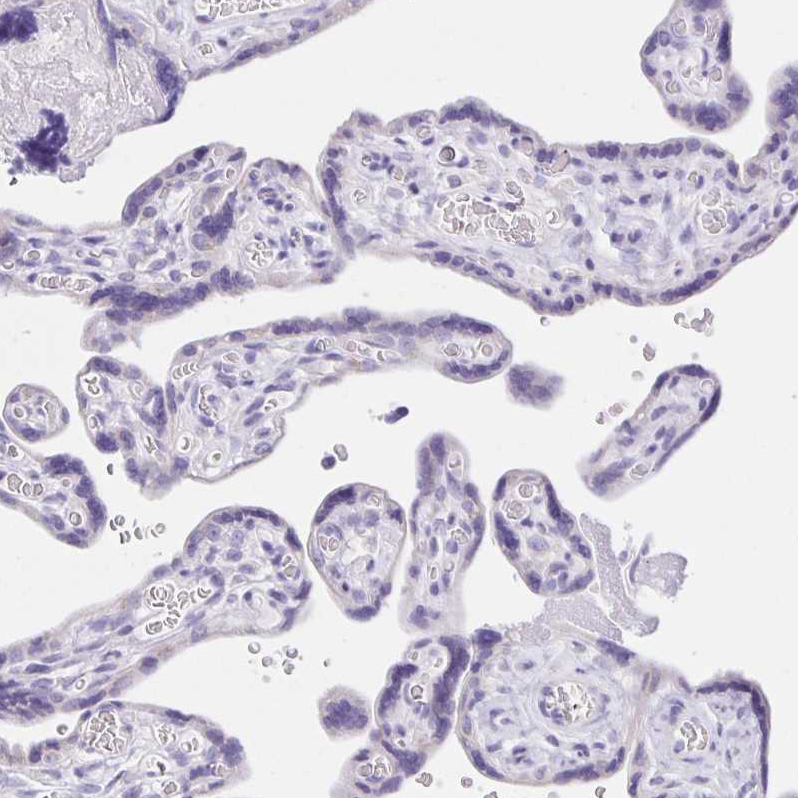

Immunohistochemical staining of human pancreas shows strong membranous positivity in islets of Langerhans.